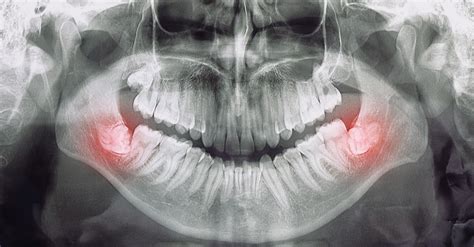

Sí, una muela del juicio que está erupcionando o con un diente formando debajo puede causar inflamación e infección en los tejidos blandos que rodean la encía. Esta situación se produce con frecuencia cuando la muela no tiene suficiente espacio para salir correctamente o lo hace de forma parcial, dejando una parte cubierta por encía. Los síntomas más comunes incluyen dolor dental localizado, hinchazón, dificultad para abrir la boca o masticar, e incluso fiebre si la infección progresa. Ante estos signos, es fundamental acudir cuanto antes a la clínica dental. No ignores los síntomas.